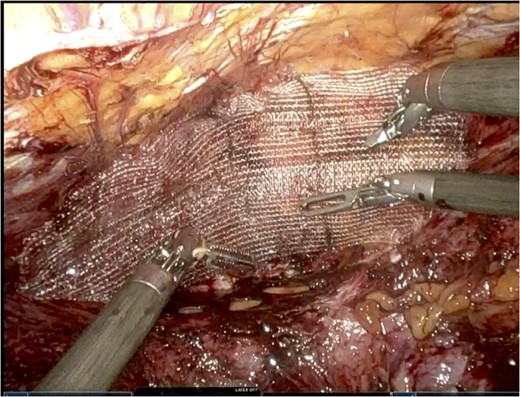

Polypropylene ProGrip mesh was then cut to size to cover the primary defect. It was cut to 14 cm in horizontal dimension by 7 cm in vertical dimension, with rounded edges (Fig. 5).

Once it was in an appropriate position to cover the defect, attention was turned to the peritoneal flap closure with a running 3–0 V-Loc suture.